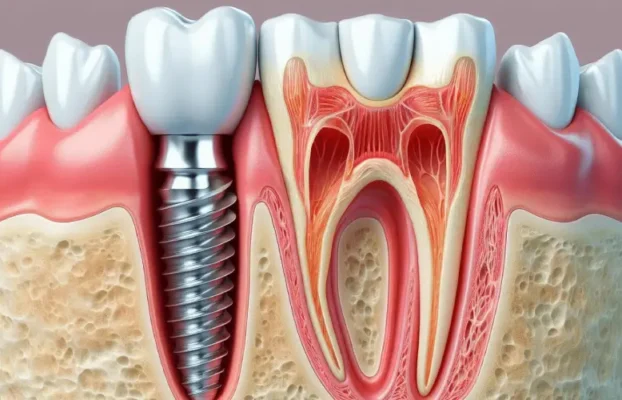

جراحی ایمپلنت دندان می تواند جایگزین خوبی برای دندان های از دست رفته باشد. این روش شامل کاشت یک پایه فلزی در استخوان فک و پس از آن قرار دادن روکش دندان بروی آن است.

عملکرد ایمپلنت های دندانی به لحاظ ساختاری مشابه دندان انسان می باشند. ایمپلنت دندان انواع متفاوتی دارد و انواع ایمپلنت بر اساس کارایی و جایگاه هرکدام متفاوت است. در این مقاله از کلینیک دندانپزشکی لبخند تلاش کردیم به سوالات شما پاسخ می دهیم.

قرار دادن ایمپلنت دندان شامل جراحی برای قرار دادن یک پایه فلزی در استخوان فک شما است. با گذشت زمان (معمولاً 6 ماه) پست با استخوان اطراف خود پیوند می یابد. این به عنوان یک لنگر برای نگه داشتن یک یا چند دندان از دست رفته در جای خود عمل می کند.